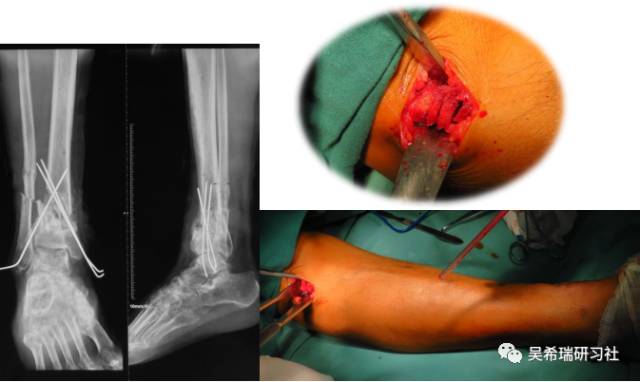

男  43岁 从2米处摔伤  开放性Pilon骨折

TIPS:关节内骨折非跨越关节固定技术一期应用骨水泥 + 开放植骨技术腓骨克氏针固定技术截骨矫形胫骨近端取骨技术